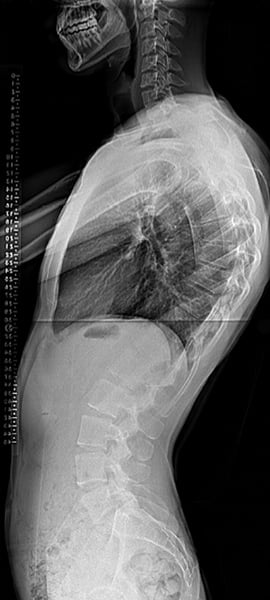

Radiographs of a patient with Scheuermann’s kyphosis who underwent corrective surgery (spinal fusion with instrumentation).

Scheuermann’s disease, also known as Scheuermann’s kyphosis, was originally described in Northern European male teenagers. In contrast to patients with postural kyphosis, patients with Scheuermann’s disease have abnormalities in the thoracic vertebrae and the discs. Specifically, some of their thoracic vertebrae are trapezoidal in shape, a defining feature of the disease. This leads to a kyphosis that is structural and can be treated surgically if it is severe.

When surgery is indicated, as is often the case in Scheuermann’s kyphosis, an orthopedic surgeon will restore physiologic alignment to the spine by performing one or more of the following procedures: removing abnormal discs, fusing the affected vertebrae together, and placing instrumentation in the spine as needed to maintain correct posture while the vertebrae fuse together.

A posterior surgical approach (accessing spine from the back) is the most common method. However, patients with a large, rigid curve may also require an additional procedure with an anterior approach (through the chest).